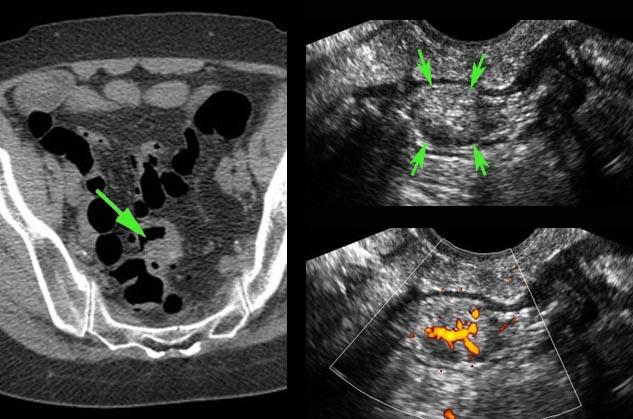

Polyp tuyến

Một polyp đại tràng (mũi tên) được phát hiện trên cả CT và nội soi đại tràng, tuy nhiên do tình trạng gập góc liên quan đến dính ruột, polyp nằm ngoài tầm với của dụng cụ sinh thiết.

Các bác sĩ phẫu thuật cần thêm bằng chứng trước khi tiến hành cắt đoạn ruột qua nội soi ổ bụng.

TVUS cho thấy một khối trong lòng ruột, hình bầu dục, đặc, bờ rõ, không đồng nhất, tăng sinh mạch máu (mũi tên) với đường kính 1,5 cm.

Bệnh nhân được phẫu thuật cắt đoạn ruột, kết quả giải phẫu bệnh cho thấy polyp tuyến ác tính.